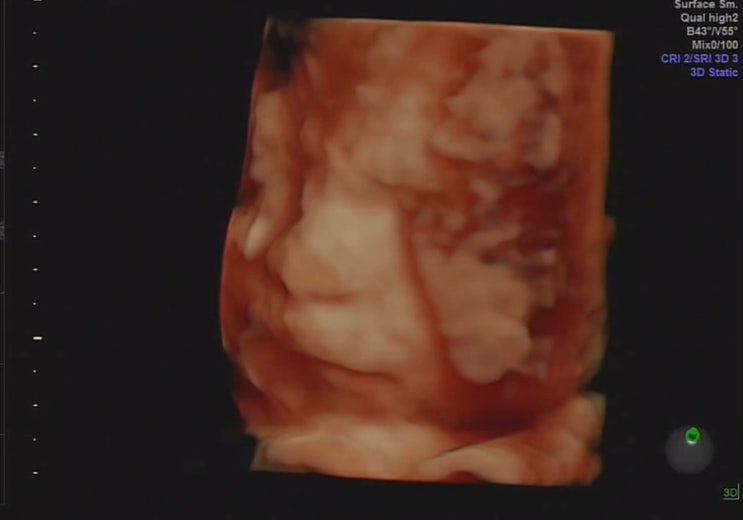

(임신후기) 28주~30주|2차정밀입체초음파|역아|실패후기|산전육아휴직|육아휴직답례품

안녕하세요! 오늘은 3번 병원 방문하였으나 입체 초음파 실패한 후기입니다? ?1차 시도? 28주 1일...